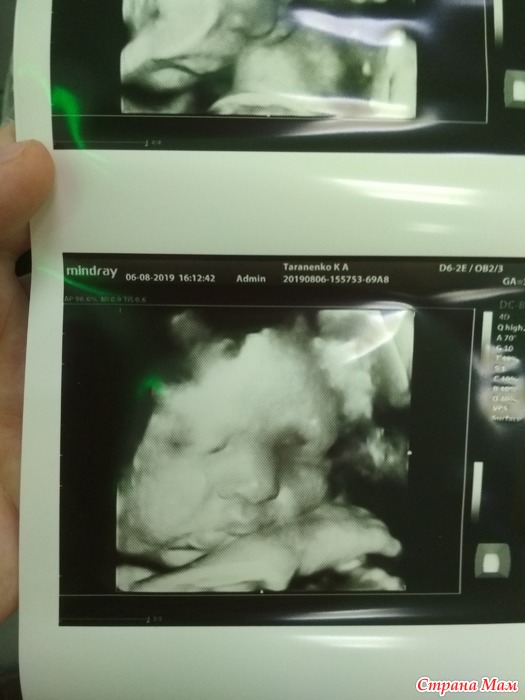

На 37 неделе. 36 недель и 5 дней.

Дочка 8 августа, сын 9 августа.

2780 и 50 см. Пока забрали, набюдают как недоношенного. Сердце материнское не спокойно.